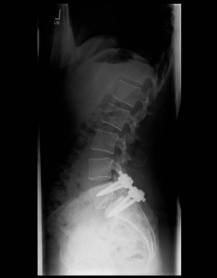

X-ray image of a slipped vertebra in the lower lumbar spine before and after surgery